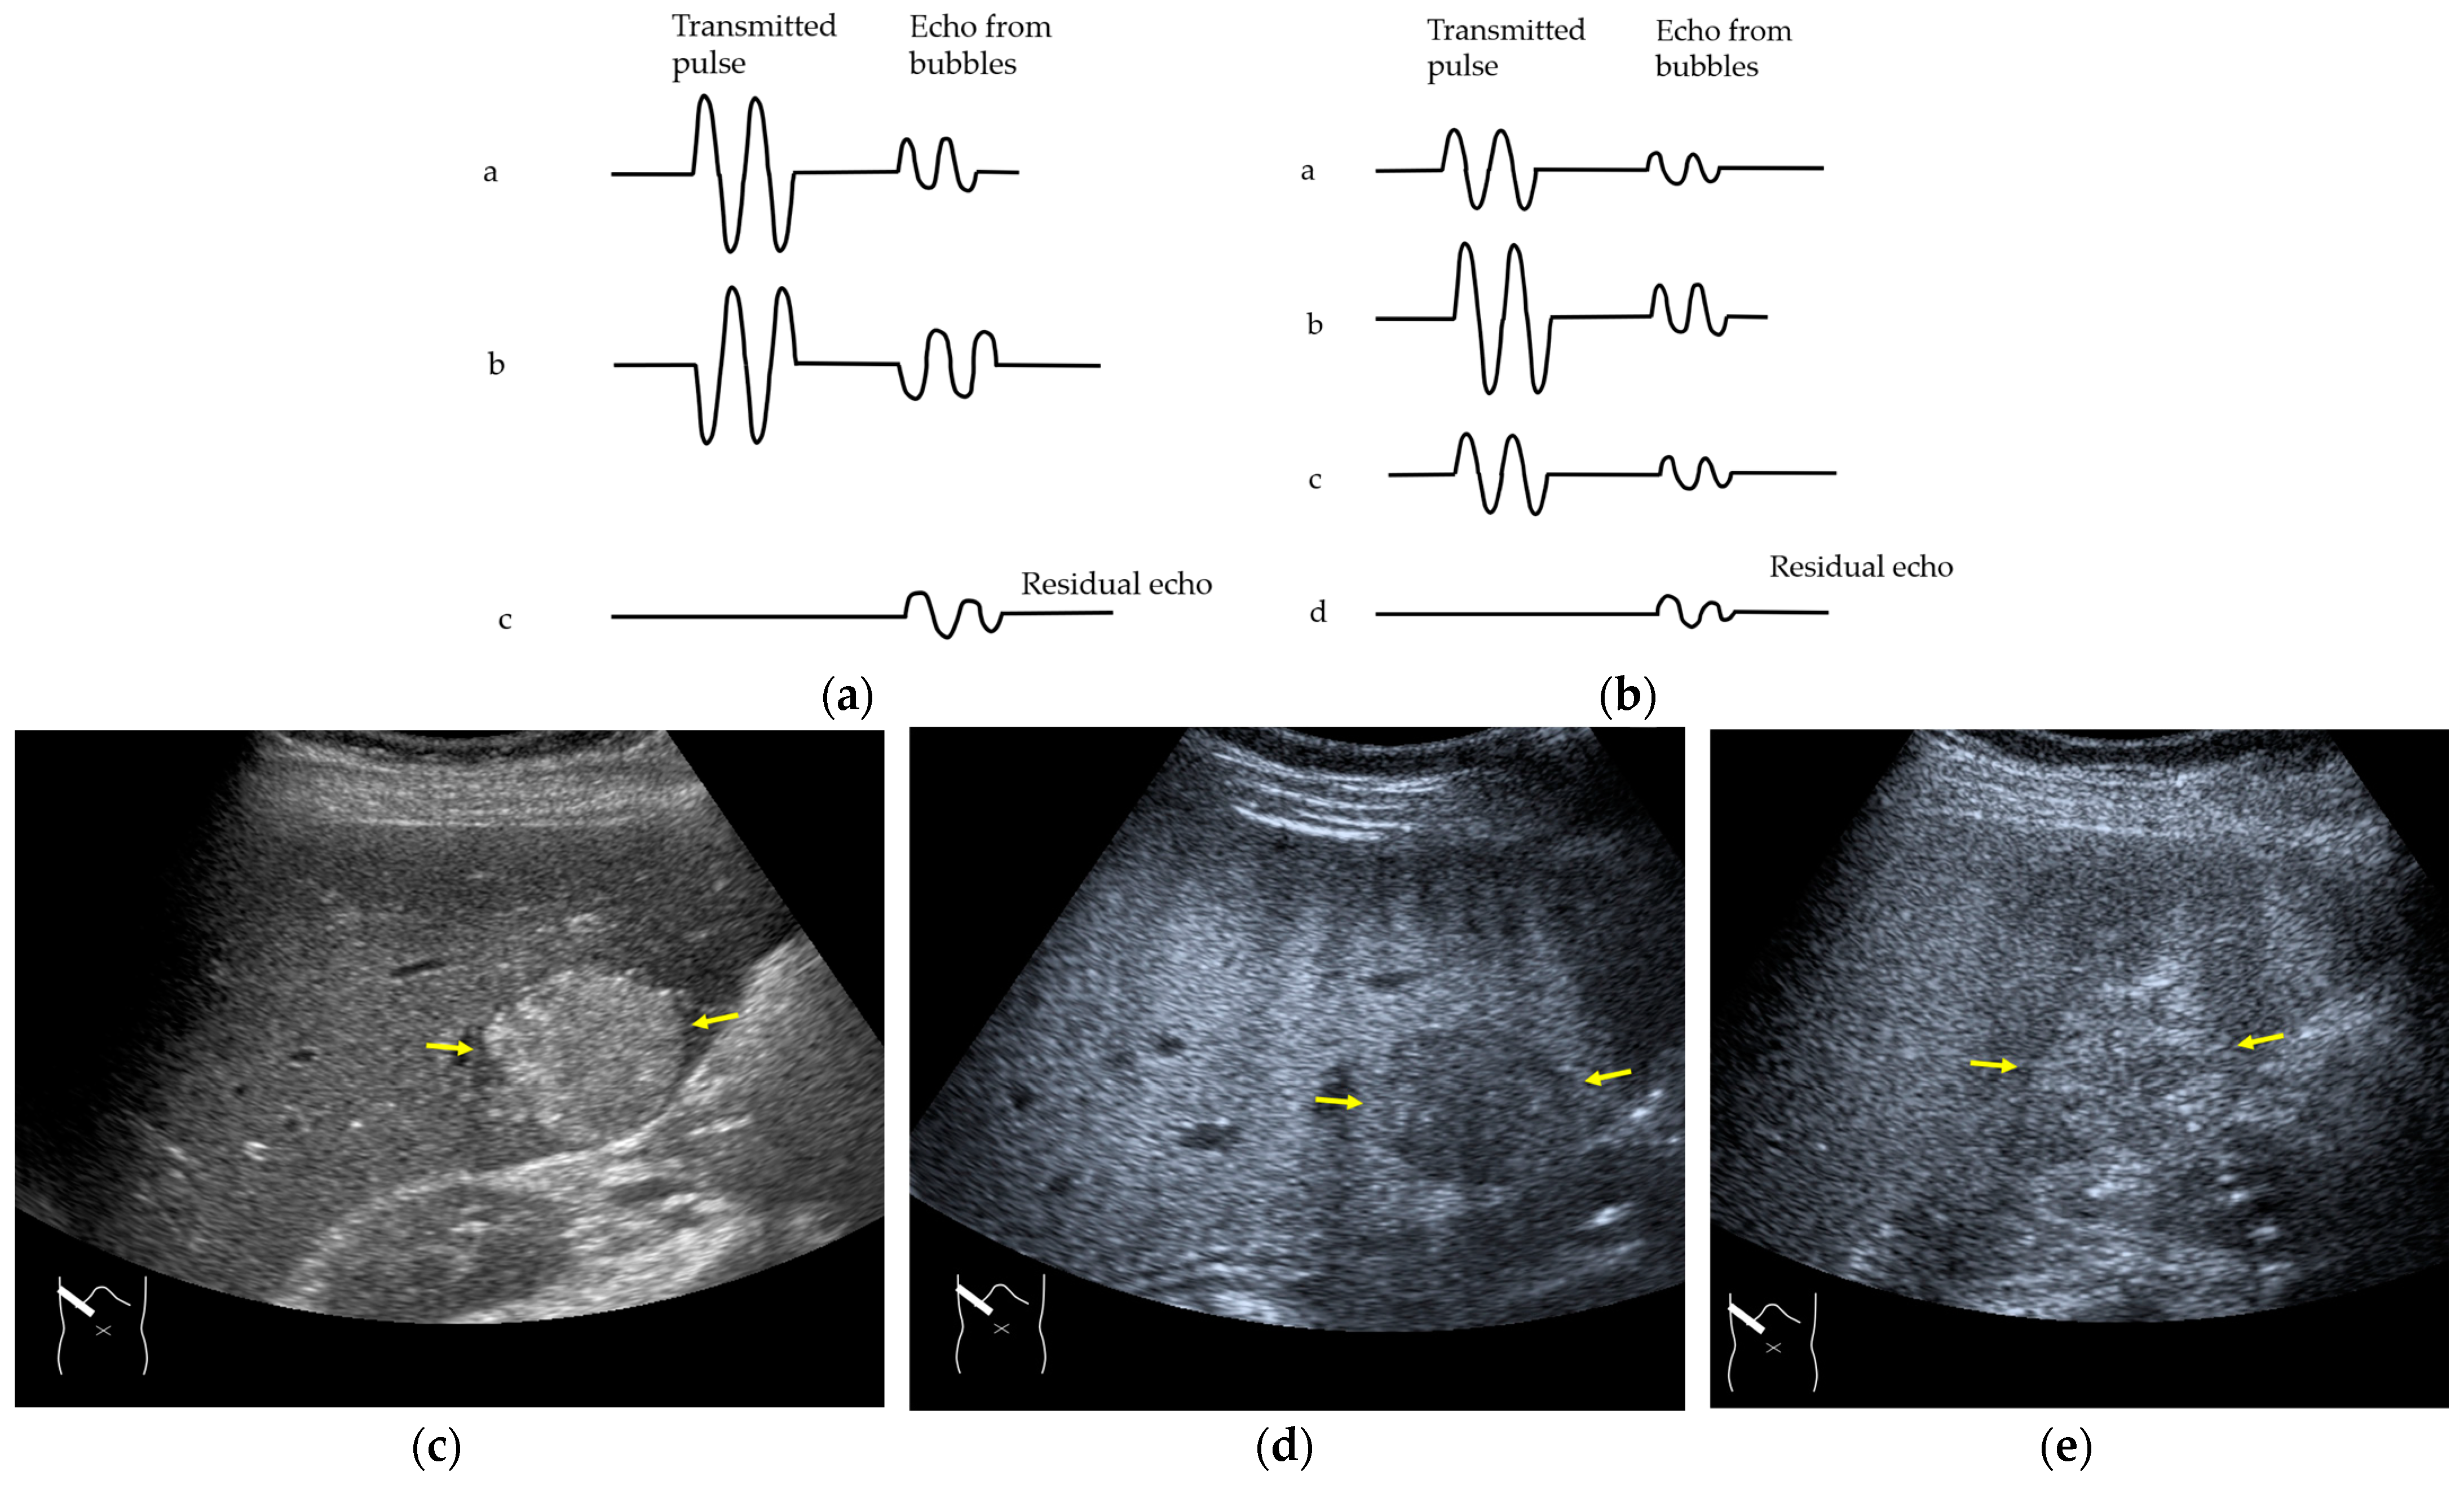

3.2.1. Microbubble Destruction Artifacts

- Quaia, E. Contrast-specific imaging techniques: Technical perspective. In Contrast Media in Ultrasonography, 1st ed.; Baert, A.L., Sartor, K., Eds.; Springer-Verlag: Berlin/Heidelberg, Germany; New York, NY, USA, 2005; pp. 43–70. [Google Scholar]

- Claudon, M.; Cosgrove, D.; Albrecht, T.; Bolondi, L.; Bosio, M.; Calliada, F.; Correas, J.M.; Darge, K.; Dietrich, C.; D’Onofrio, M.; et al. Guidelines and good clinical practice recommendations for contrast enhanced ultrasound (CEUS)—Update 2008. Ultraschall Med. 2008, 29, 28–44. [Google Scholar] [CrossRef]

- Claudon, M.; Dietrich, C.F.; Choi, B.I.; Cosgrove, D.O.; Kudo, M.; Nolsøe, C.P.; Piscaglia, F.; Wilson, S.R.; Barr, R.G.; Chammas, M.C.; et al. Guidelines and good clinical practice recommendations for Contrast Enhanced Ultrasound (CEUS) in the liver—Update 2012: A WFUMB-EFSUMB initiative in cooperation with representatives of AFSUMB, AIUM, ASUM, FLAUS and ICUS. Ultrasound Med. Biol. 2013, 39, 187–210. [Google Scholar] [CrossRef] [PubMed]